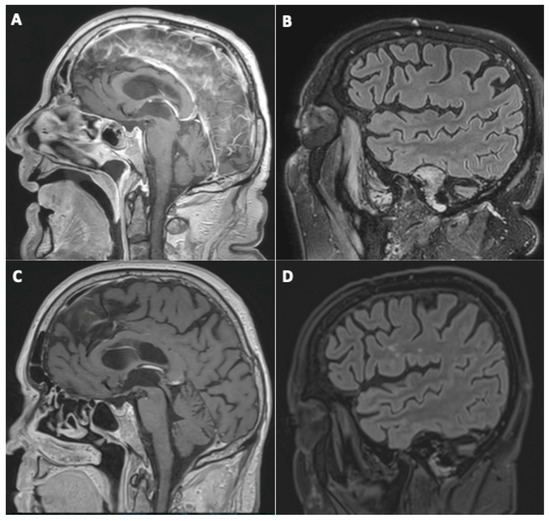

3.1. Brain MRI Findings

- Evolution of initial neuroimaging findings

- New findings during follow-up

- Evolution of perfusion imaging